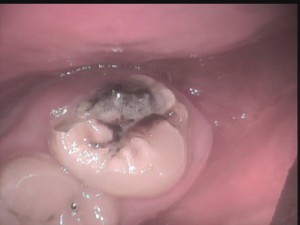

でも、「虫歯って言われたけど自覚症状ないし、本当に虫歯なのかなあ?」と疑問に思う場合の対処法としては、削る前に、「口腔内カメラ」で見せてもらうこと。

上の奥歯だと、鏡では見えにくいですが、口腔内カメラならバッチリ見えます。

それで、納得した上で治療を受けられた方が我々歯科医師も患者さんも気持ちいいし。

~口腔内カメラの映像:写真は親不知ですが、鏡では見えにくい親不知の虫歯もはっきり確認できます~

まあ、口腔内カメラでも見えにくい虫歯もないわけではないのですが・・・